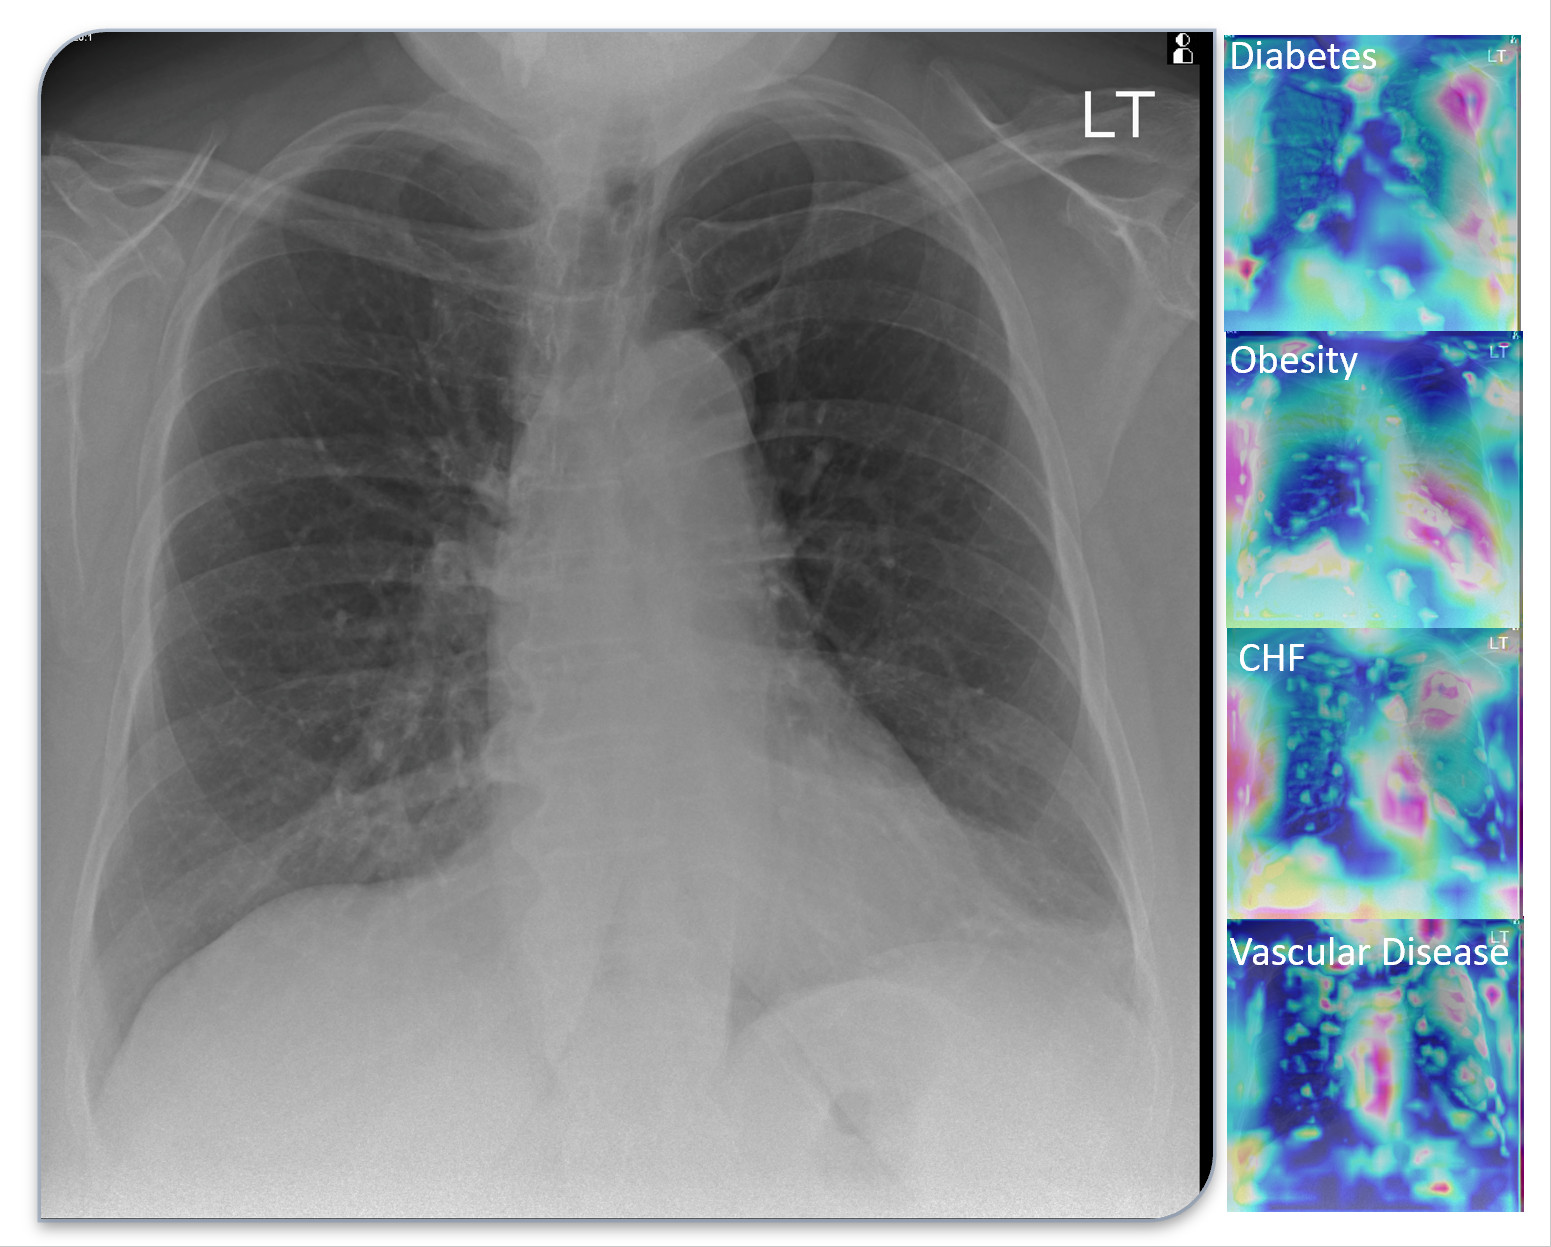

This image models a 70-year-old female patient with COVID19 hospitalized for 9-days. The deep learning model predicted diabetes, obesity, congestive heart failure and vascular disease, which were verified upon chart review, but several of these conditions were only found after extensive chart searching.

Specifically, the AI reads an X-ray and accounts for six medical variables, including:

• Diabetes with chronic complications

• Obesity, or a BMI over 40

• Congestive heart failure, or an enlarged heart on the X-ray

• Cardiac arrhythmia, such as atrial fibrillation

• Vascular disease, including atherosclerosis, calcifications, plaques, etc.

• Lung disease, such as COPD